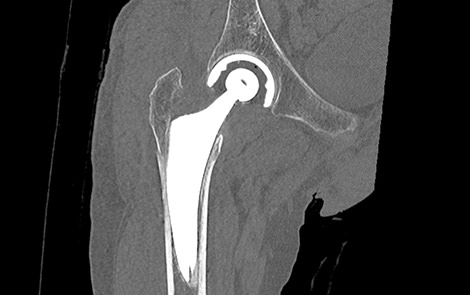

16列マルチスライスCT装置 Aquilion Lightning(キャノンメディカルシステムズ製)を導入しており骨折の診断、手術前計画目的の撮影、骨癒合経過観察目的で検査を行っています。CTでは撮影した元データより様々な断面の画像を再構成(MPR画像)でき、骨の外観のような三次元的な画像(VR画像)も作成でき、レントゲンでは評価しづらい細かい骨折の診断などにも優れています。撮影時間は数分で終わります。